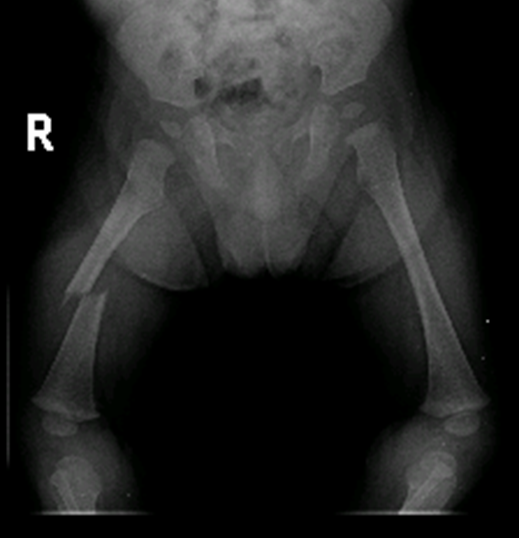

How we'll treat your child's hip fracture depends on the location, complexity and severity of his break — as well as his. Fracture of upper portion of femur (anywhere from femoral head to about 5 cm below lesser trochanter), typically resulting in groin and thigh pain;

If fracture is displaced, affected extremity generally appears shortened (with hip positioned in external rotation and abduction). What are the symptoms of a hip fracture? The majority of accidental humeral fractures in children are supracondylar and the commonest abusive humeral fracture in children <5 years are spiral or oblique.

In children <12 months old, ss is necessary regardless of the fracture type or reported hx with rare exceptions. Fortunately, most hip fractures in children heal without a problem. The garden classification of subcapital femoral neck fractures is the most widely used. The exception to this protocol was in two delbet's type iv (intertr … April 2011 joshua klatt, md; Epidemiology of fractures in children. This introduction provides the speed and accuracy of operation. Hip fractures in children constitute less than 1% of all hip fractures and are usually the result of a highenergy trauma. How we'll treat your child's hip fracture depends on the location, complexity and severity of his break — as well as his. Osteosynthesis with three screws in the hip fracture in young patients. Fractures and dislocations about the hip in the pediatric patient joshua klatt, md original author: Effect of early hip decompression on the frequency of avascular necrosis in children with fractures of the neck of the femur. It is estimated that each year 1.6% to 2.1% of all the children sustain a fracture. Hip fractures are also more common in women, who are more likely to get osteoporosis, a condition which makes bones weak and fragile. About 15% of all injuries in children are fracture injuries. Diminished estrogen production makes postmenopausal women more susceptible to osteoporosis and hip fractures — in fact, women make up 70 percent of all hip fracture patients. Hip fractures are classified according to their anatomical location as intracapsular, which involves the femoral head and neck, and extracapsular, which includes intertrochanteric, trochanteric, an.